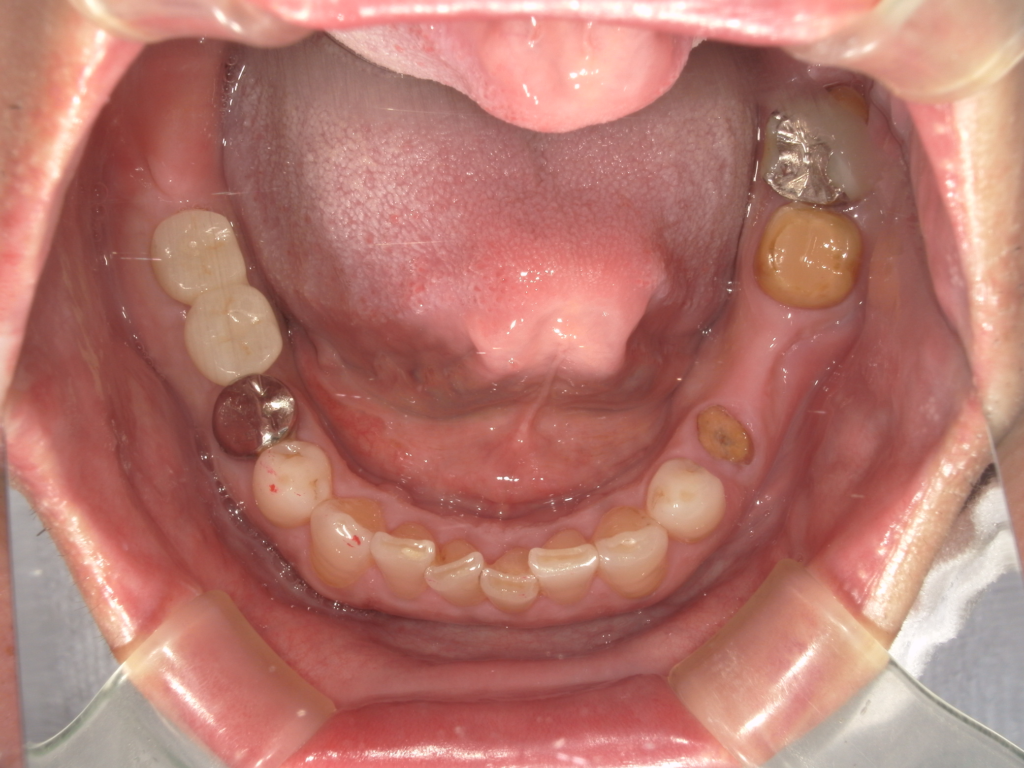

Y様インプラント実例 #44

左の上下の奥歯をインプラントで治療しています。

左下の奥歯は歯を抜くのと同時にインプラントの埋め込みを行っています。

被せものは上下、セラミックスで作っています。

治療前

治療後